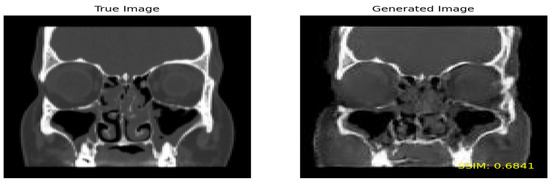

Perceptual Similarity: In contrast to the SSIM, which measures the overall similarity between two images, perceptual similarity assesses how similar images are perceived by humans. This means that a fake image exhibiting high visual resemblance to a true image may receive a high perceptual similarity score, even if its structural similarity score is comparatively low. Figure 8 shows the true image on the left and the generated image on the right by including the SSIM value on the lower part of the image.

• SSIM

In the evaluation process for the ‘Moderate’ class, an SSIM threshold of 0.6 and above was applied to retain the generated images displaying the highest similarity to the true images. Out of a total of 852,640 combinations, 717 images exhibited a similarity greater than 0.6 and were consequently selected.

Figure 8. Comparison of true and generated images with SSIM.